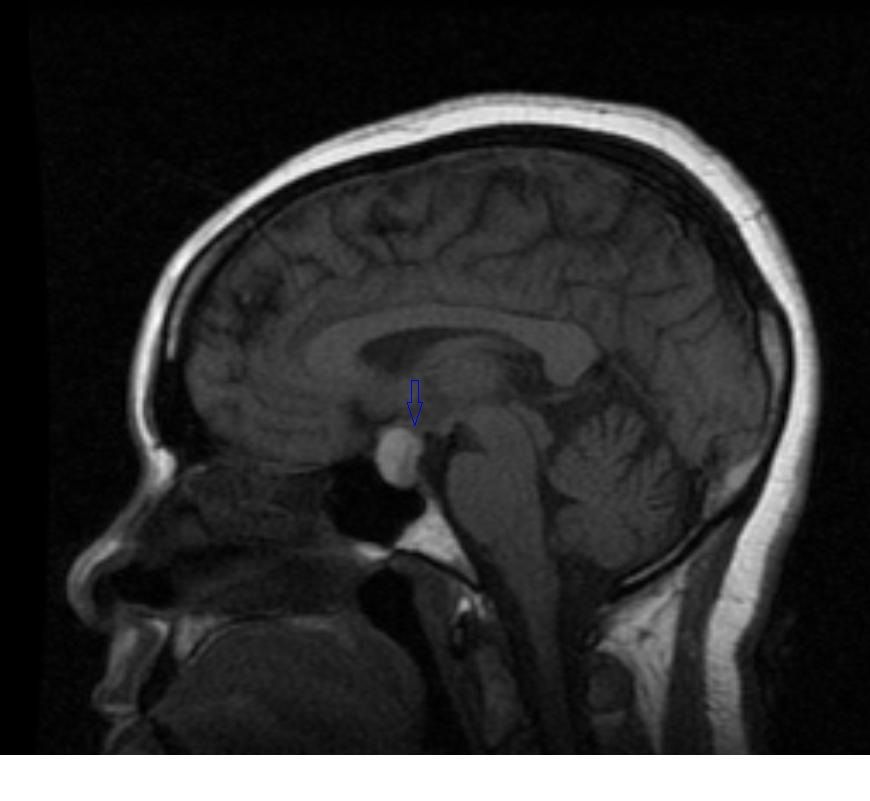

Figure A4: Sagittal T1-weighted image showing a macroadenoma in the sella extending superiorly (blue arrow), with an area of relatively low signal intensity in the posterior pituitary.

The initial brain scans were obtained 6 months after her initial diagnosis (3 months into her pregnancy) and revealed a hemorrhagic pituitary macroadenoma (Figures A1-4). The patient recollects that a week before the scan, she suffered an episode of severe headache with visual disturbance of the right eye. She did not seek medical attention at the time but did keep an appointment for the brain imaging the following week. At the time of the imaging, she reported that her symptoms had fully resolved.

She remained asymptomatic at her clinic follow-up 2 weeks after the episode, and there were no objective focal neurologic deficits. Full ophthalmologic assessment was unremarkable, with no visual field defects. She remained asymptomatic without neurologic deficits and, so far, has no features of hypopituitarism. Repeated scans performed 6 months into the patient’s pregnancy (Figures B1-4; cuts are equivalent to A series) did not show any significant interval changes. She gave birth at 9 months uneventfully and is being followed up regularly for signs and symptoms of hypopituitarism.